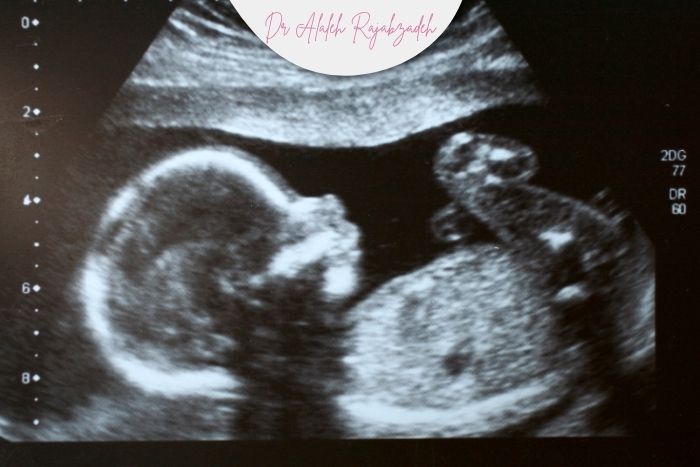

ناهنجاریهای قابل تشخیص در سونوگرافی

در سونوگرافی میتوان برخی از مشکلات مربوط به مغز و ستون فقرات جنین را زودتر از زمان تولد شناسایی کرد. این ناهنجاریها گاهی باعث اختلال در رشد مغز، جمجمه یا نخاع میشوند.عدم تشکیل بخشهایی از مغز و جمجمه (آننسفالی): در این حالت بخشهایی از سر جنین شکل نمیگیرد و در سونوگرافی بهوضوح دیده میشود.